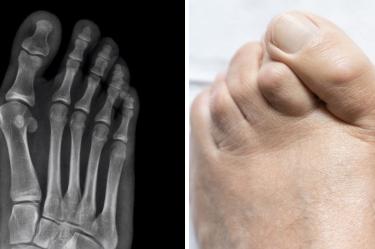

La palabra juanete proviene del término griego “nabo”. Cuando se forman juanetes, surgen porque los huesos de la articulación MTF se desplazan, inclinándose sobre los otros dedos. La articulación MTF aumenta y sobresale.

Son protuberancias óseas que se forman en las articulaciones en la base de los dedos gordos de los pies. Sucede cuando algunos huesos de la parte frontal del pie, se mueven de lugar. Como resultado, la punta del dedo gordo se dirige hacia los otros dedos y origina cambios en las articulaciones. Por fuera, la piel puede notarse roja y se siente dolor.

De acuerdo al Manual MSD, se le conoce como hallux valgus a la dolencia en la que la base del dedo gordo se orienta de forma anormal hacia afuera y la punta del dedo va hacia adentro. En la base del dedo puede crecer hueso extra y un saco con líquido. Los juanetes son más comunes en las mujeres por el uso de zapatos de punta estrecha o tacón alto.